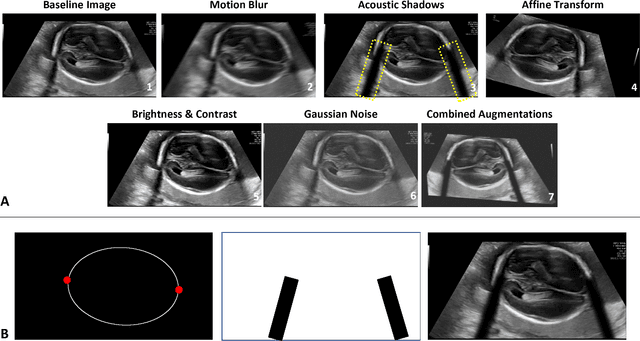

Abstract:Quality assessment of prenatal ultrasonography is essential for the screening of fetal central nervous system (CNS) anomalies. The interpretation of fetal brain structures is highly subjective, expertise-driven, and requires years of training experience, limiting quality prenatal care for all pregnant mothers. With recent advancement in Artificial Intelligence (AI), specifically deep learning (DL), assistance in precise anatomy identification through semantic segmentation essential for the reliable assessment of growth and neurodevelopment, and detection of structural abnormalities have been proposed. However, existing works only identify certain structures (e.g., cavum septum pellucidum, lateral ventricles, cerebellum) from either of the axial views (transventricular, transcerebellar), limiting the scope for a thorough anatomical assessment as per practice guidelines necessary for the screening of CNS anomalies. Further, existing works do not analyze the generalizability of these DL algorithms across images from multiple ultrasound devices and centers, thus, limiting their real-world clinical impact. In this study, we propose a DL based segmentation framework for the automated segmentation of 10 key fetal brain structures from 2 axial planes from fetal brain USG images (2D). We developed a custom U-Net variant that uses inceptionv4 block as a feature extractor and leverages custom domain-specific data augmentation. Quantitatively, the mean (10 structures; test sets 1/2/3/4) Dice-coefficients were: 0.827, 0.802, 0.731, 0.783. Irrespective of the USG device/center, the DL segmentations were qualitatively comparable to their manual segmentations. The proposed DL system offered a promising and generalizable performance (multi-centers, multi-device) and also presents evidence in support of device-induced variation in image quality (a challenge to generalizibility) by using UMAP analysis.